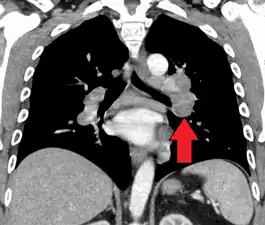

CT scan of the chest showing lymphadenopathy (arrows) in the mediastinum due to sarcoidosis

Diagnosis of sarcoidosis is a matter of exclusion, as there is no specific test for the condition. To exclude sarcoidosis in a case presenting with pulmonary symptoms might involve a chest radiograph, CT scan of chest, PET scan, CT-guided biopsy, mediastinoscopy, open lung biopsy, bronchoscopy with biopsy, endobronchial ultrasound, and endoscopic ultrasound with fine-needle aspiration of mediastinal lymph nodes (EBUS FNA). Tissue from biopsy of lymph nodes is subjected to both flow cytometry to rule out cancer and special stains (acid fast bacilli stain and Gömöri methenamine silver stain) to rule out microorganisms and fungi.[100][101][12][102]